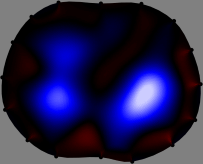

Refer to caption

Figure 2: Fidelity-embedded regularization method. (Left bottom) Correlations between four different column vectors (𝐒ksubscript𝐒𝑘{\bf S}_{k}) and all the remaining column vectors (𝐒subscript𝐒{\bf S}_{\ell}) are visualized. (Right bottom) Performances of the proposed fidelity-embedded regularization method for λ=𝜆\lambda=\infty are shown by numerical simulations.

To explain the FER method, we closely examine the correlations among column vectors of the sensitivity matrix 𝕊𝕊\mathbb{S}, described in Fig. 2. The correlation between 𝐒ksubscript𝐒𝑘{\bf S}_{k} and 𝐒subscript𝐒{\bf S}_{\ell} can be expressed as

for i=1,,16𝑖116i=1,\cdots,16[23]. This shows that the column vector 𝐒ksubscript𝐒𝑘{\bf S}_{k} is like an EEG (electroencephalography) data induced by dipole sources with directions uj,j=1,,16formulae-sequencesubscript𝑢𝑗𝑗116\nabla u_{j},j=1,\cdots,16 at locations ΔksubscriptΔ𝑘\Delta_{k}. Given that two dipole sources at distant locations produce mutually independent data, the correlation between 𝐒ksubscript𝐒𝑘\mathbf{S}_{k} and 𝐒subscript𝐒\mathbf{S}_{\ell} decreases with the distance between ΔksubscriptΔ𝑘\Delta_{k} and ΔsubscriptΔ\Delta_{\ell}. Fig. 2 shows a few images of the correlation 𝐒k,𝐒(|𝐒k||𝐒|)1subscript𝐒𝑘subscript𝐒superscriptsubscript𝐒𝑘subscript𝐒1\left\langle\mathbf{S}_{k},\mathbf{S}_{\ell}\right\rangle(|\mathbf{S}_{k}||\mathbf{S}_{\ell}|)^{-1} as a function of \ell for four different positions ΔksubscriptΔ𝑘\Delta_{k}. The correlation decreases rapidly as the distance increases. In the green regions where the correlation is almost zero, 𝐒subscript𝐒{\bf S}_{\ell} is nearly orthogonal to 𝐒ksubscript𝐒𝑘{\bf S}_{k}.